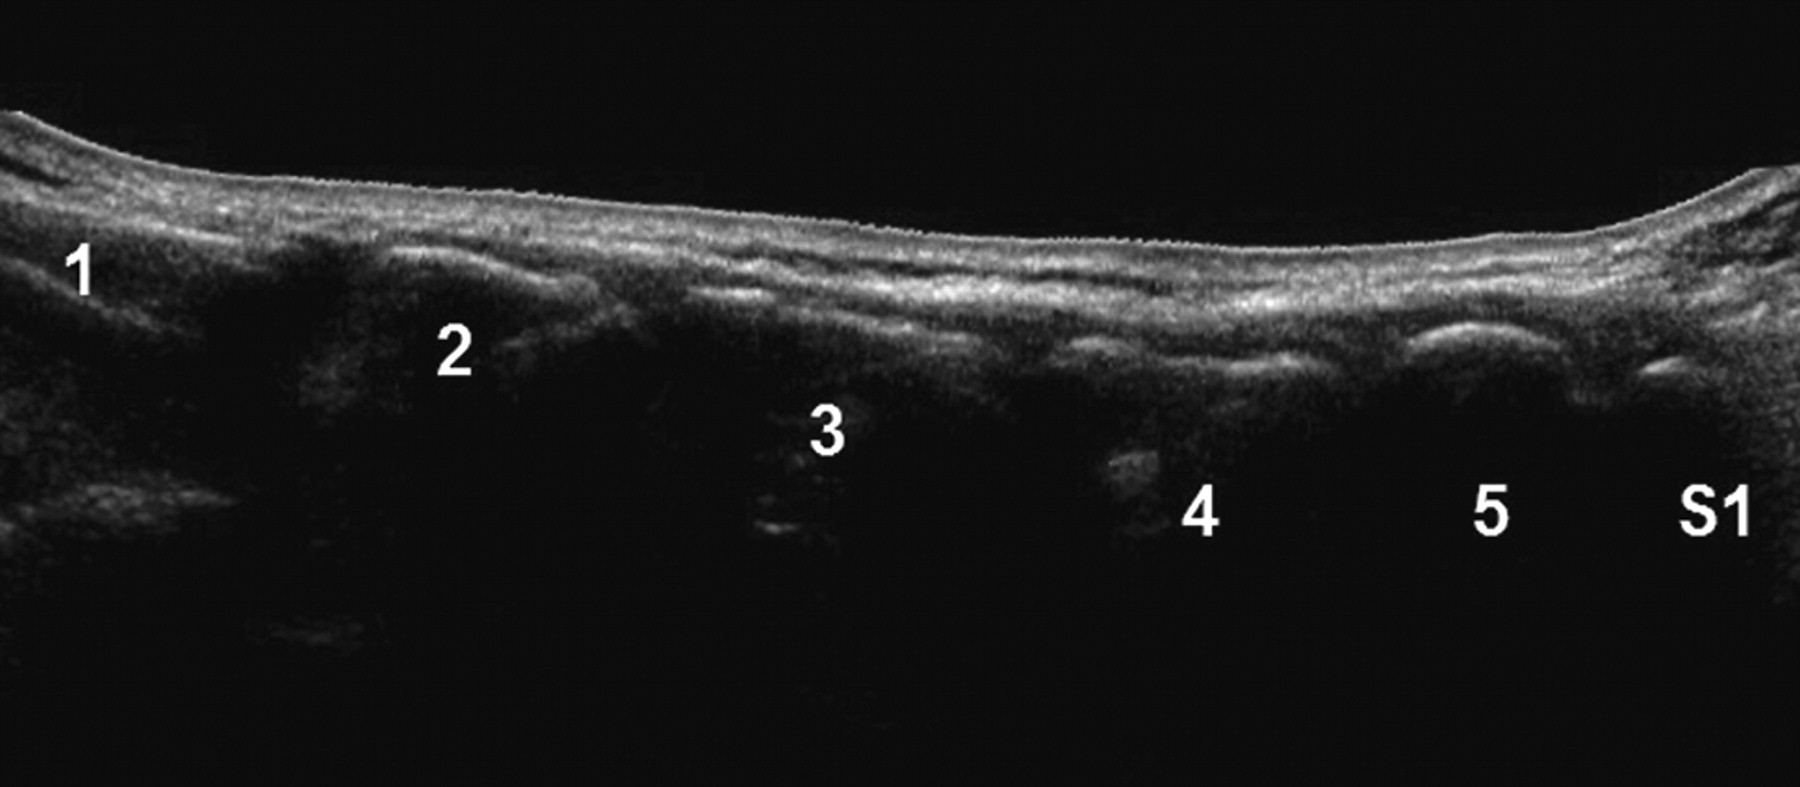

US image of pararadicular injection (PAP) at levels L2-L3 showing delineation of the needle, needle tip, intertransverse ligament, and costal processes.